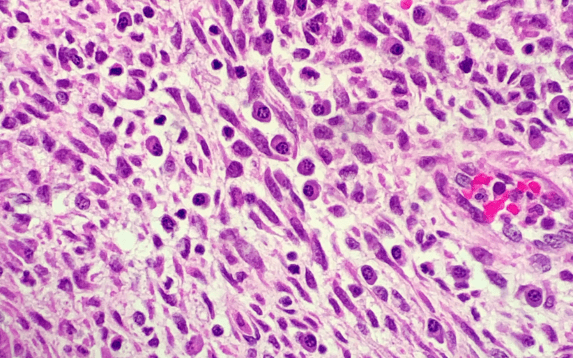

Accurate diagnosis is the first step toward effective treatment. At ISHA IVF & Fertility Center, doctors use advanced diagnostic tools such as endometrial biopsy, hysteroscopy, and microbial cultures to detect inflammation. Endometrial tissue analysis helps confirm the presence of plasma cells, the hallmark of chronic endometritis. Timely and precise diagnosis ensures targeted therapy and faster recovery.